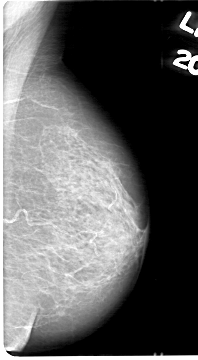

D_4044_1.LEFT_MLO

LEFT_MLO LINES 5386 PIXELS_PER_LINE 2956 BITS_PER_PIXEL 12 RESOLUTION 43.5 NON_OVERLAY